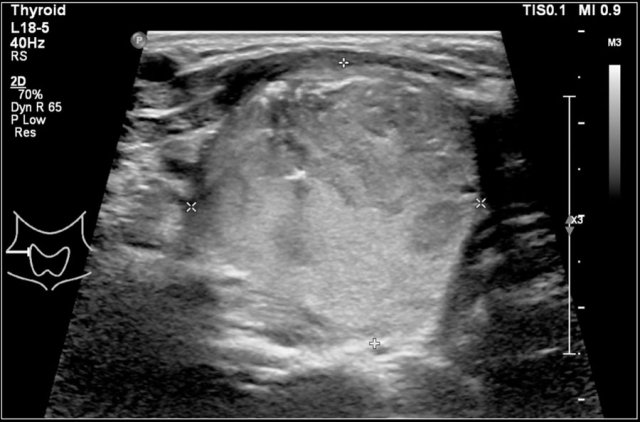

Thyroiditis

The most common forms of thyroiditis are Hashimoto's thyroiditis and Graves disease.

Both Hashimoto's thyreoiditis and Graves disease can present as an enlarged and hyperemic thyroid.

Hashimoto's thyroiditis or chronic lymphocytic thyroiditis is an auto-immune disease.

It presents with hypothyroidism.

Although primarily a disease of the middle-aged it can present in children.

On ultrasound the gland is diffusely enlarged and inhomogeneous.

On color doppler the blood flow is often normal but can be increased like in Graves' disease.

In a later stage the gland shrinks.

Here an image of a 16-year-old girl with hyperthreoidism.

A diffusely enlarged thyroid gland is seen with hyperemia.

The final diagnosis was Graves disease.

She was treated with I-131.